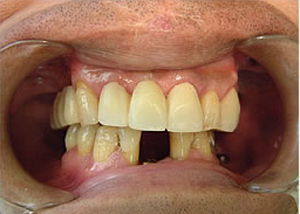

症例1 51歳男性

治療前

平成16年7月7日

3.仮歯上12本

下15本入れたところ(正面)

-正面-下14本の最終の冠をかぶせたところ

治療完了

平成19年5月1日

(治療期間:2年10ヶ月)